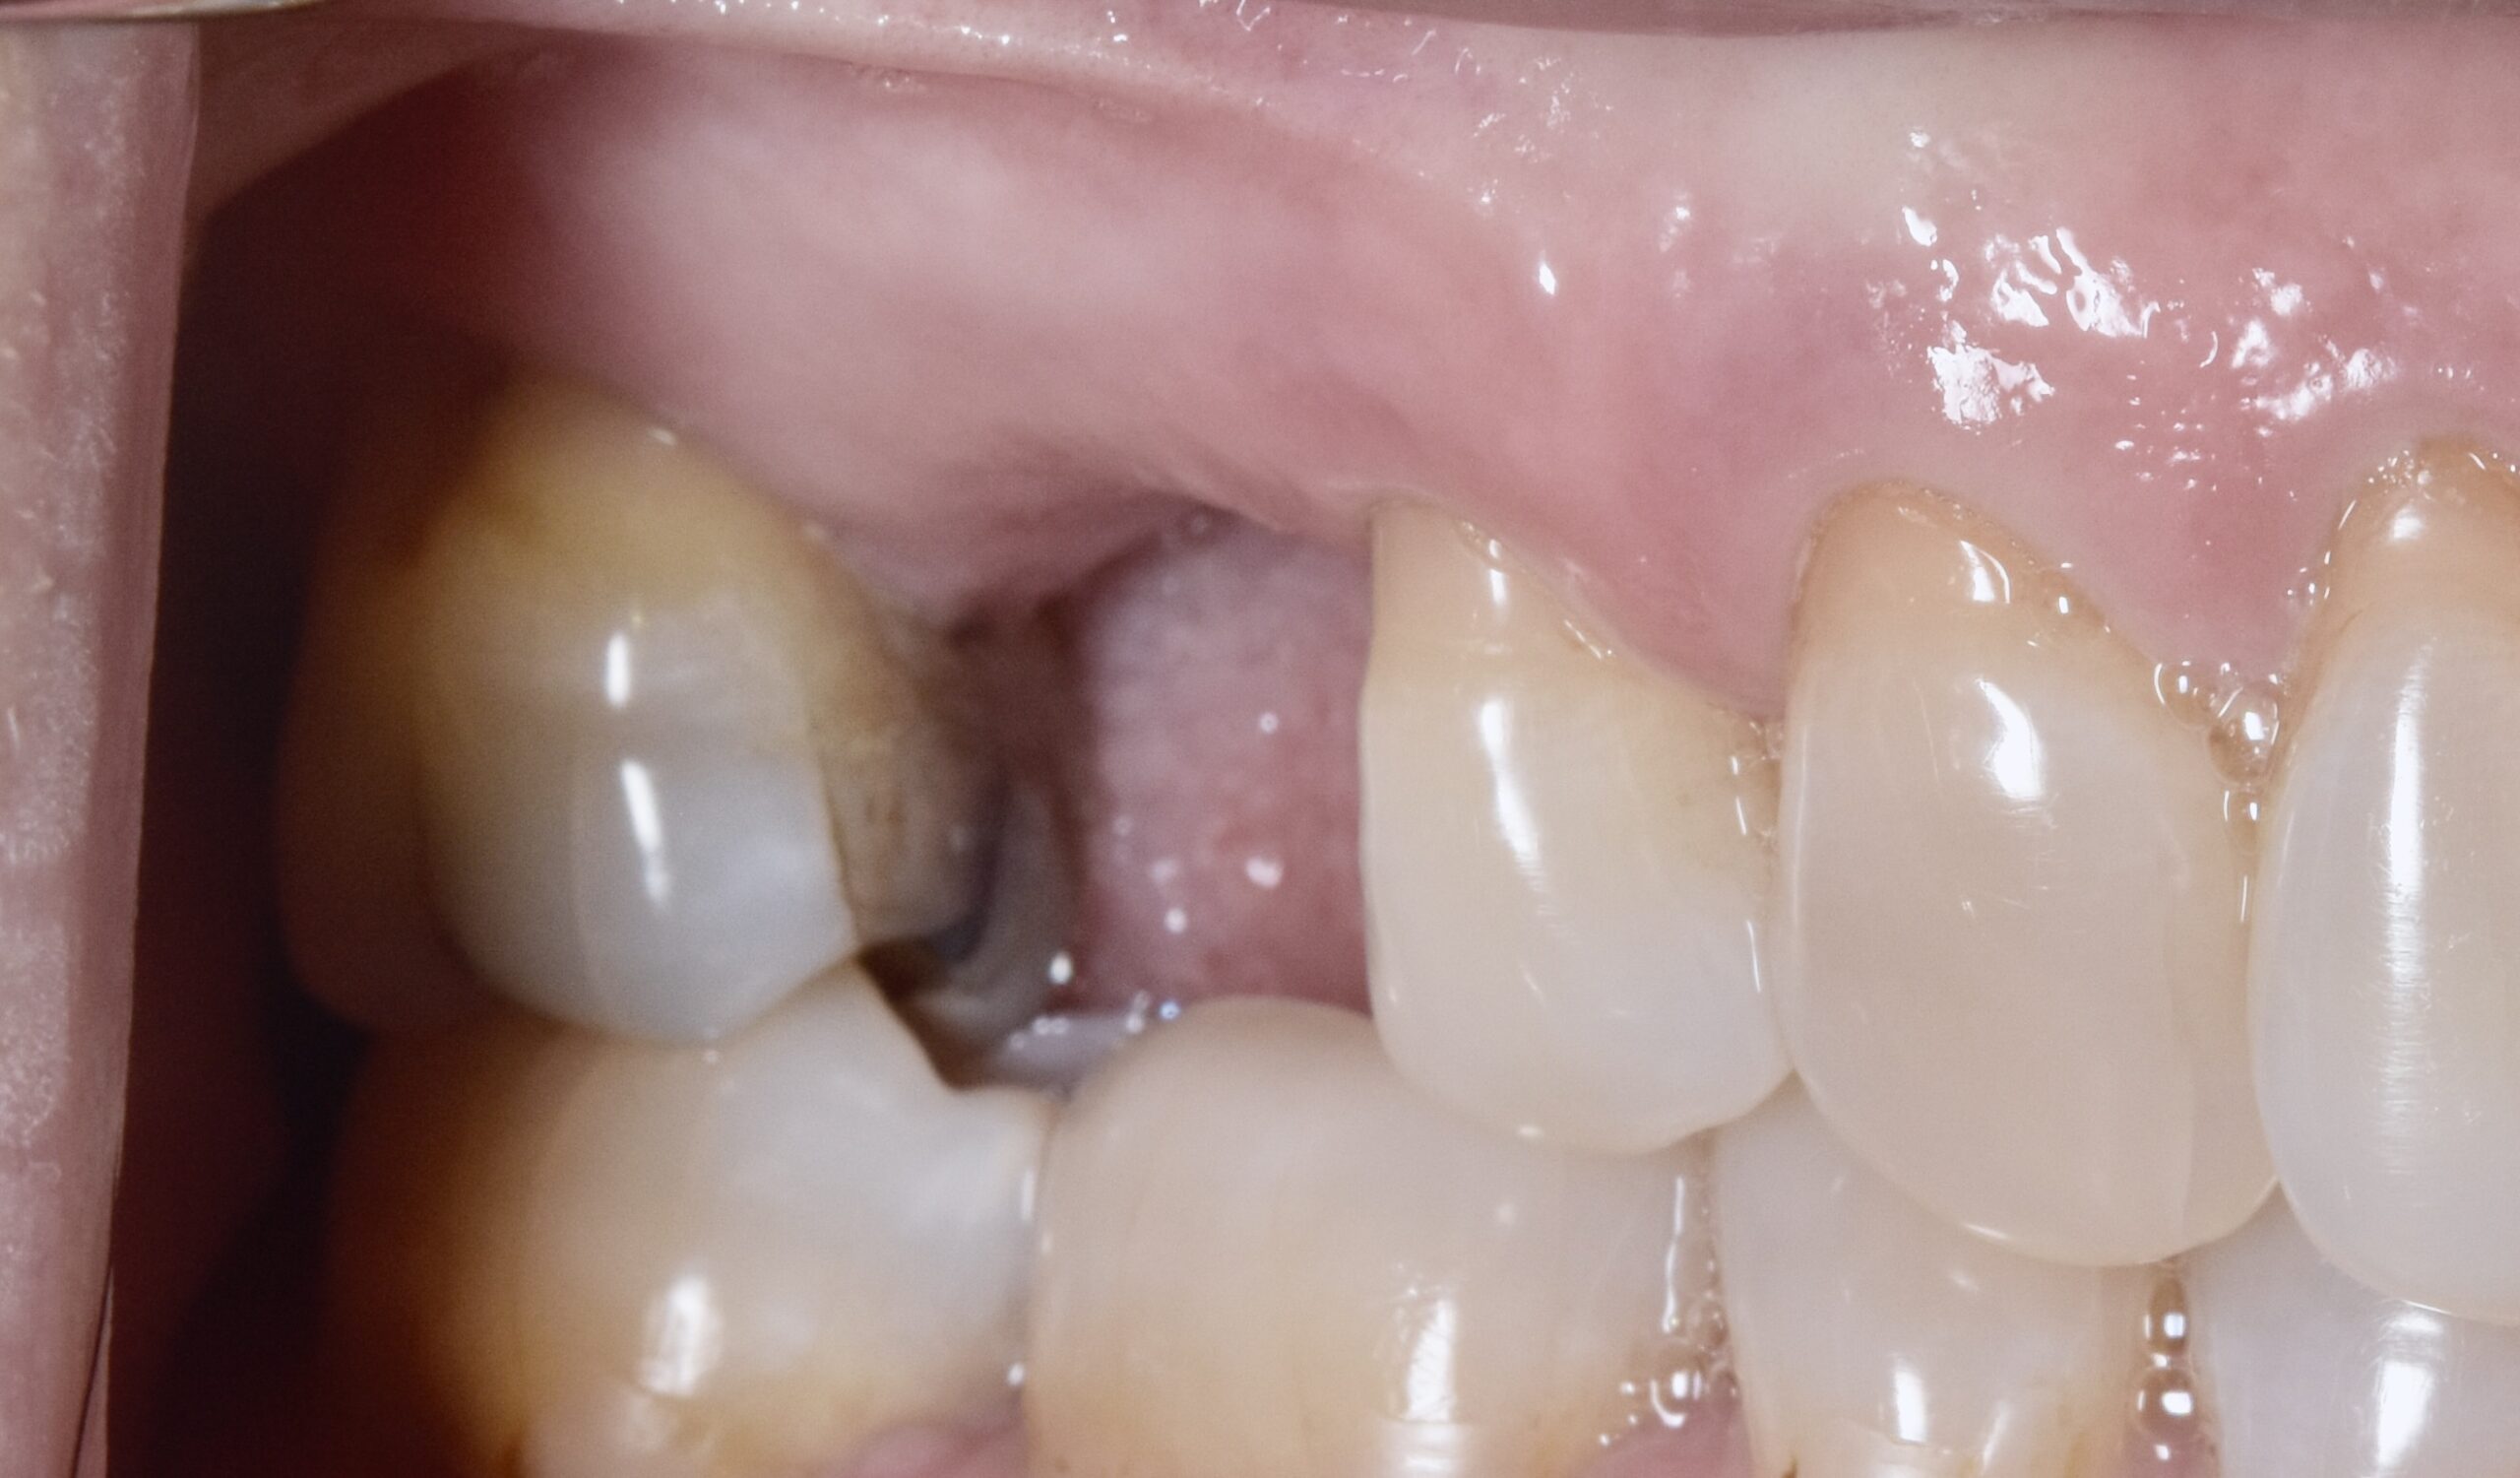

初診時

術後